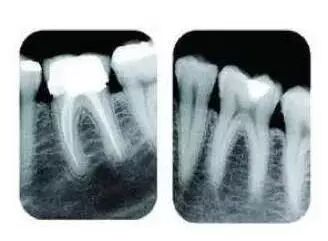

比如当牙齿有深部龋坏时,仅凭口内检查无法得知龋洞的深度、离牙神经的距离以及有没有并发牙根发炎等重要信息

要了解个别牙根及周围变化,则选择拍摄小牙片。医生要判断牙槽骨是否符合种植条件,或者了解埋伏阻生齿的三维位置以及其他颌骨内病变组织的形态大小时,则需要进一步拍摄 CBCT 。

所以,拍牙片是一种帮助齿科医生进行诊断、治疗、疗效评估的重要手段,治疗前用于发现病变程度、范围;治疗中用于引导治疗、确定治疗范围和深度;治疗后用于观察疗效。